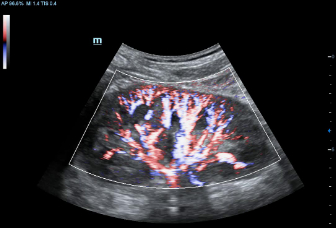

–ú–Ω–æ–≥–æ—Ñ—É–Ω–∫—Ü–∏–æ–Ω–∞–ª—å–Ω–∞—è —Å–∏—Å—Ç–µ–º–∞ DC-60 Exp —Å X-Insight –ø—Ä–µ–¥—Å—Ç–∞–≤–ª—è–µ—Ç —Å–æ–±–æ–π –∫–æ–º–ø–ª–µ–∫—Å–Ω–æ–µ —Ä–µ—à–µ–Ω–∏–µ, –∫–æ—Ç–æ—Ä–æ–µ –ø–æ–º–æ–≥–∞–µ—Ç —É–ø—Ä–∞–≤–ª—è—Ç—å –ø–æ–≤—Å–µ–¥–Ω–µ–≤–Ω–æ–π –∫–ª–∏–Ω–∏—á–µ—Å–∫–æ–π –ø—Ä–∞–∫—Ç–∏–∫–æ–π —Å –ª–µ–≥–∫–æ—Å—Ç—å—é –∏ —É–≤–µ—Ä–µ–Ω–Ω–æ—Å—Ç—å—é.

–û—Å–Ω–æ–≤—ã–≤–∞—è—Å—å –Ω–∞ –≥–ª—É–±–æ–∫–æ–º –ø–æ–Ω–∏–º–∞–Ω–∏–∏ –ø–æ—Ç—Ä–µ–±–Ω–æ—Å—Ç–µ–π –∫–ª–∏–µ–Ω—Ç–æ–≤, –∫–æ–º–ø–∞–Ω–∏—è Mindray —Ä–∞–∑—Ä–∞–±–æ—Ç–∞–ª–∞ —Å–∏—Å—Ç–µ–º—É DC-60 Exp —Å X-Insight, —á—Ç–æ–±—ã –æ–±–µ—Å–ø–µ—á–∏—Ç—å –≤—ã—Å–æ–∫—É—é –ø—Ä–æ–∏–∑–≤–æ–¥–∏—Ç–µ–ª—å–Ω–æ—Å—Ç—å –∏ —Ç–æ—á–Ω–æ—Å—Ç—å –≤–∏–∑—É–∞–ª–∏–∑–∞—Ü–∏–∏ –≤–∫—É–ø–µ —Å –Ω–∞–≥–ª—è–¥–Ω–æ—Å—Ç—å—é, –∏—Å–∫–ª—é—á–∏—Ç–µ–ª—å–Ω–æ–π –∏–Ω—Ç–µ–ª–ª–µ–∫—Ç—É–∞–ª—å–Ω–æ—Å—Ç—å—é –∏ –æ–≥—Ä–æ–º–Ω—ã–º –æ–ø—ã—Ç–æ–º.